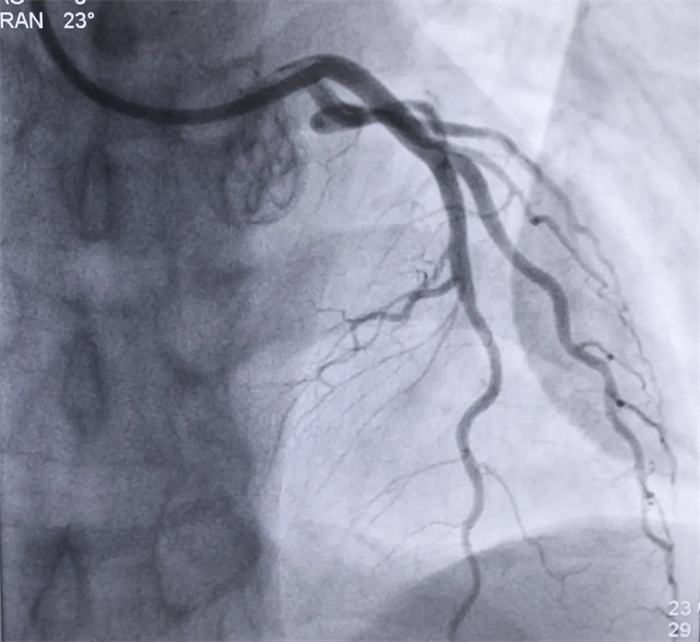

術(shù)后冠脈造影

心血管內(nèi)科主任朱永彪得到消息后,第一時間做好了手術(shù)準備工作。上午11點零6分,患者被推入導(dǎo)管室,急診PCI介入治療即刻開始:冠脈造影顯示,該患者左前降支近中斷完全閉塞并伴有血栓影,經(jīng)過術(shù)中短暫討論,行前降支介入治療。血栓抽吸后,于前降支中斷植入生物可降解支架。行血管內(nèi)超聲檢查后,可見支架貼壁良好,管腔基本恢復(fù)正常。最終造影顯示支架擴張滿意,無殘余狹窄,前向血流TIMI3級,患者胸痛癥狀得到明顯改善。目前,該患者生命體征正常,正在ICU接受進一步觀察治療。